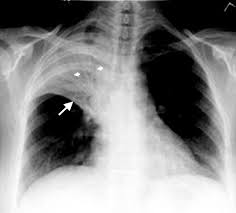

πνευμονία δεξιού άνω λοβού. ομότιμη σκίαση με περιορισμένη μείωση του ακτινολογικού όγκου του λοβού, με αεροβρογχόγραμμα.

λοβώδης πνευμονία δεξιού μέσου λοβού. προκαλεί θετικό σημείο σιλουέττας με τα δεξιά όρια της καρδιάς. Αεροβρογόγραμμα

Η εξιδρωματική διήθηση στην ακτινογραφία θώρακος είναι αναγκαία για την απεικονιστική τεκμγηρίωση της πνευμονίας κοινότητας, κι επομένως, πρέπει νδιενεργείται σε κάθε ασθενή με υποψία πνευμονίας.

Η έκταση των ακτινολογικών ευρημάτων εισφέρει στην αποτύπωση της βαρύτητας της νόσου και συνεπικουρεί στην λήψη των αρχικών αποφάσεων. Η λοβώδης πύκνωση η εκσκαφή, και η πλευριτική συλλογή υποδηλώνουν την μικροβιακή φύση της πνευμονίας, ενώ η διάχυτη παρεγχυματική επινέμηση συνηθέστερα συσχετίζεται με λεγεωνέλλα ή ιογενή λοίμωξη. Για την τεκμηρίωση της πνευμνονίας κοινότητας, απαιτείται η αναγνώριση πυκνώσεως στην -συνήθως- απλή ακτινογραφία θώρακος (&). Η έκταση των ακτινολογικών ευρημάτων εισφέρει στην ταυτοποίηση της βαρύττηας της παθήσεως και στη λήψη αποφάσεων σχετικά με τον τρόπου διαχειρίσεώς της. Η λοβαία πύκνωση, η παρουσία κοιλοτήτων, και η παραπνευμονική πλευριτική συλογή, είναι ευρήματα, δηλωτικά μικροβιακής λοιμώξεως, ενώ, αντίθιετα, η διάχυτη κατανομή, αμτφοτερόπλευρη, προσιδιάζουν σε λοίμωξη από Legionella ή σε ιογενή πνευμονία. Επειδή η υπερκατανάλωση αντιβιθοτικών για τη θεραπεία των λοιμώξεων του ανώτερου αναπνευστικού συστήματος, επάγει την ανάπτυξη ανθεκτικών περιπτώσεων, ενώ δεν είναι απαλλαγμένη παρενεργειών, η ταυτοποίηση εκείνων των ασθενών με πραγματική μικροβιακή πνευμονία είναι απαραίτητη.